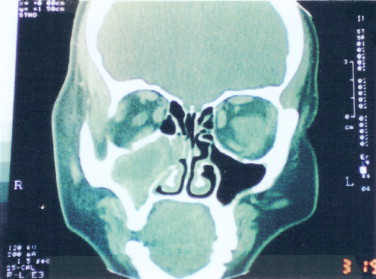

- Imaging: MRI, CT scan, and PET scan to visualize the tumor and assess its extent.

- 영상 검사: 종양의 위치를 확인하고 범위를 평가하기 위한 MRI, CT 스캔 및 PET 스캔.